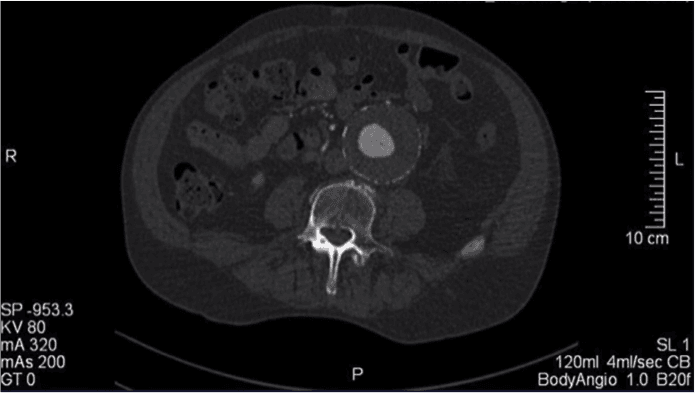

Paciente masculino, 72 años, con queja de dolor abdominal continuo enmesogástrio hace 3 días refractaria a analgésicos convencionales. En el examen físico, se encuentra normal hemodinámicamente y pres…

Paciente masculino, 72 anos, com queixa de dor abdominal contínua em mesogástrio há 3 dias refratária a analgésicos convencionais. No exame físico, encontra-se normal hemodinamicamente e presença de m…